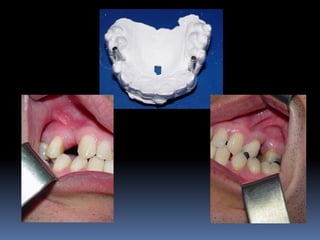

Modelos de estudo

Enceramento diagnóstico

Guia cirúrgica

Visão espacial do planejamento a

executar

•Articulados

•Projetar opções de terapêutica desde incisões,

delimitar áreas de reconstrução óssea,tipo de

prótese,número,distribuição, diâmetro dos implantes

•Compreensão do paciente

•Enceramento diagnóstico

•Guia cirúrgica